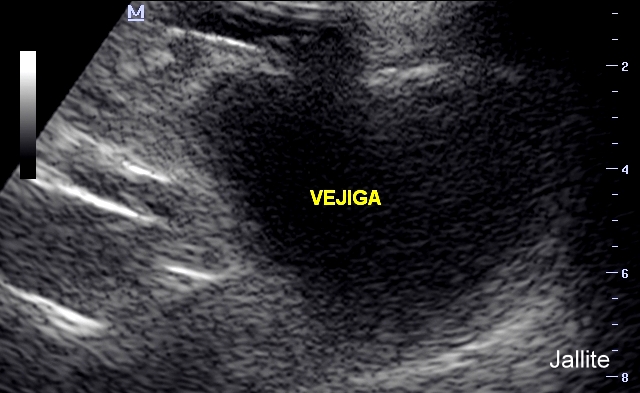

En medicina, se denomina nefrocalcinosis a la existencia de depósitos de calcio en el parénquima del riñón que puedan detectarse mediante pruebas de imagen como radiografía o ecografía. No constituye una enfermedad en sí misma, sino un síntoma que puede deberse a diferentes causas, entre ellas el hiperparatiroidismo, la intoxicación por vitamina D y la acidosis tubular renal tipo I. Suele asociarse a elevación del nivel de calcio en sangre (hipercalcemia) y exceso de eliminación de calcio a través de la orina (hipercalciuria). Se detecta mediante pruebas de imagen, en la ecografía, por ejemplo, se aprecian los depósitos de sales de calcio localizados en diferentes partes del riñón como la médula renal y la papila renal.